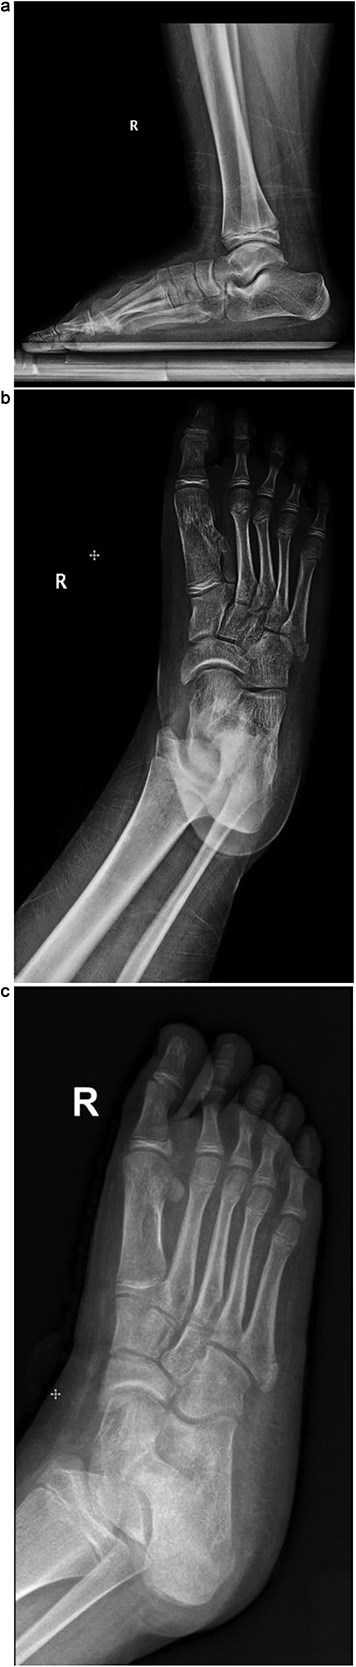

Plain radiographs revealed a bony mass extending from the medial cuneiform to the first metatarsal, with the first and second intermetatarsal space widening (Fig. 1). Magnetic resonance imaging (MRI) was performed to better characterize the mass (Fig. 2). Musculoskeletal radiologists reported the presence of an abnormal rudimentary bone that was interposed between the first and second metatarsal bones, with pseudo-articulation and ankylosis with the lateral aspect of the mid-metatarsal shaft of the hallux, causing widening and deformity, suggesting a supernumerary rudimentary metatarsal bone. An osteochondroma was also considered in the differential diagnosis, but the cartilage cap was not clearly visible. As daily activities were significantly affected, the patient’s guardian preferred surgical excision over more conservative measures, which had previously been unsuccessful.

(a) Lateral radiograph of the right foot demonstrating a bony mass extending from the medial cuneiform to the first metatarsal. (b) Oblique radiograph of the right foot highlighting the abnormal bony outgrowth between the first and second metatarsals. (c) Anteroposterior radiograph showing a bony mass arising from the medial cuneiform extending toward the first metatarsal, with widening of the first intermetatarsal space.